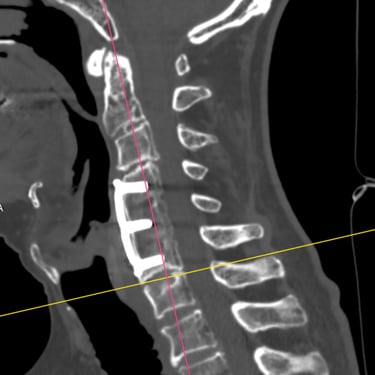

🧠 Cirugía de Revisión Cervical: Estabilidad Posterior en Seudoartrosis y Enfermedad del Segmento Adyacente.

La seudoartrosis cervical con subsidencia del cage y enfermedad del segmento adyacente genera dolor e inestabilidad. La artrodesis cervical posterior con tornillos a masas laterales y pediculares es una técnica eficaz para lograr una fijación sólida, mejorar la estabilidad y aliviar los síntomas neurológicos.